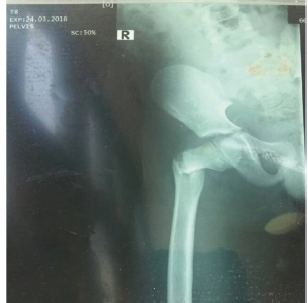

All the children had operative management either by open reduction and internal fixation (ORIF), or closed reduction and internal fixation (CRIF) under fluoroscopy since all 4 patients had displaced fractures. After patient were followed up for at least 2 years, all 4 were found to be asymptomatic clinically with no pain, no limp shortening and had no radiological evidence of AVN. Hence using the Ratliff ’s criteria, all 4 patients had good outcomes (100%) as shown in Table 2, despite 1 patient having complication of primary screw cut out on postoperative day 10 with subsequent radiograph showing implant failure (Figure 1).

Figure 1:X-ray showing failed percutaneous pinning with two cannulated screws post op.

This occurred in the 8-year-old boy who had his falling school wall landing on the right thigh whilst playing at school (Figure 2). He had closed reduction and percutaneous pinning with 2 cannulated screws without hip spica. Child was doing well post operatively on the ward until day 10 when he suddenly sat upright in a chair to receive lessons from the school teacher. He was in sudden excruciating pain and subsequent repeated radiograph confirmed the cut out of the cannulated screws (Figure 1). He later had closed reduction and percutaneous pinning with 22mm-Kirschner wire and No. 5 TiCron tension band as well as hip spica applied after previous screws removed (Figure 3 & 4).